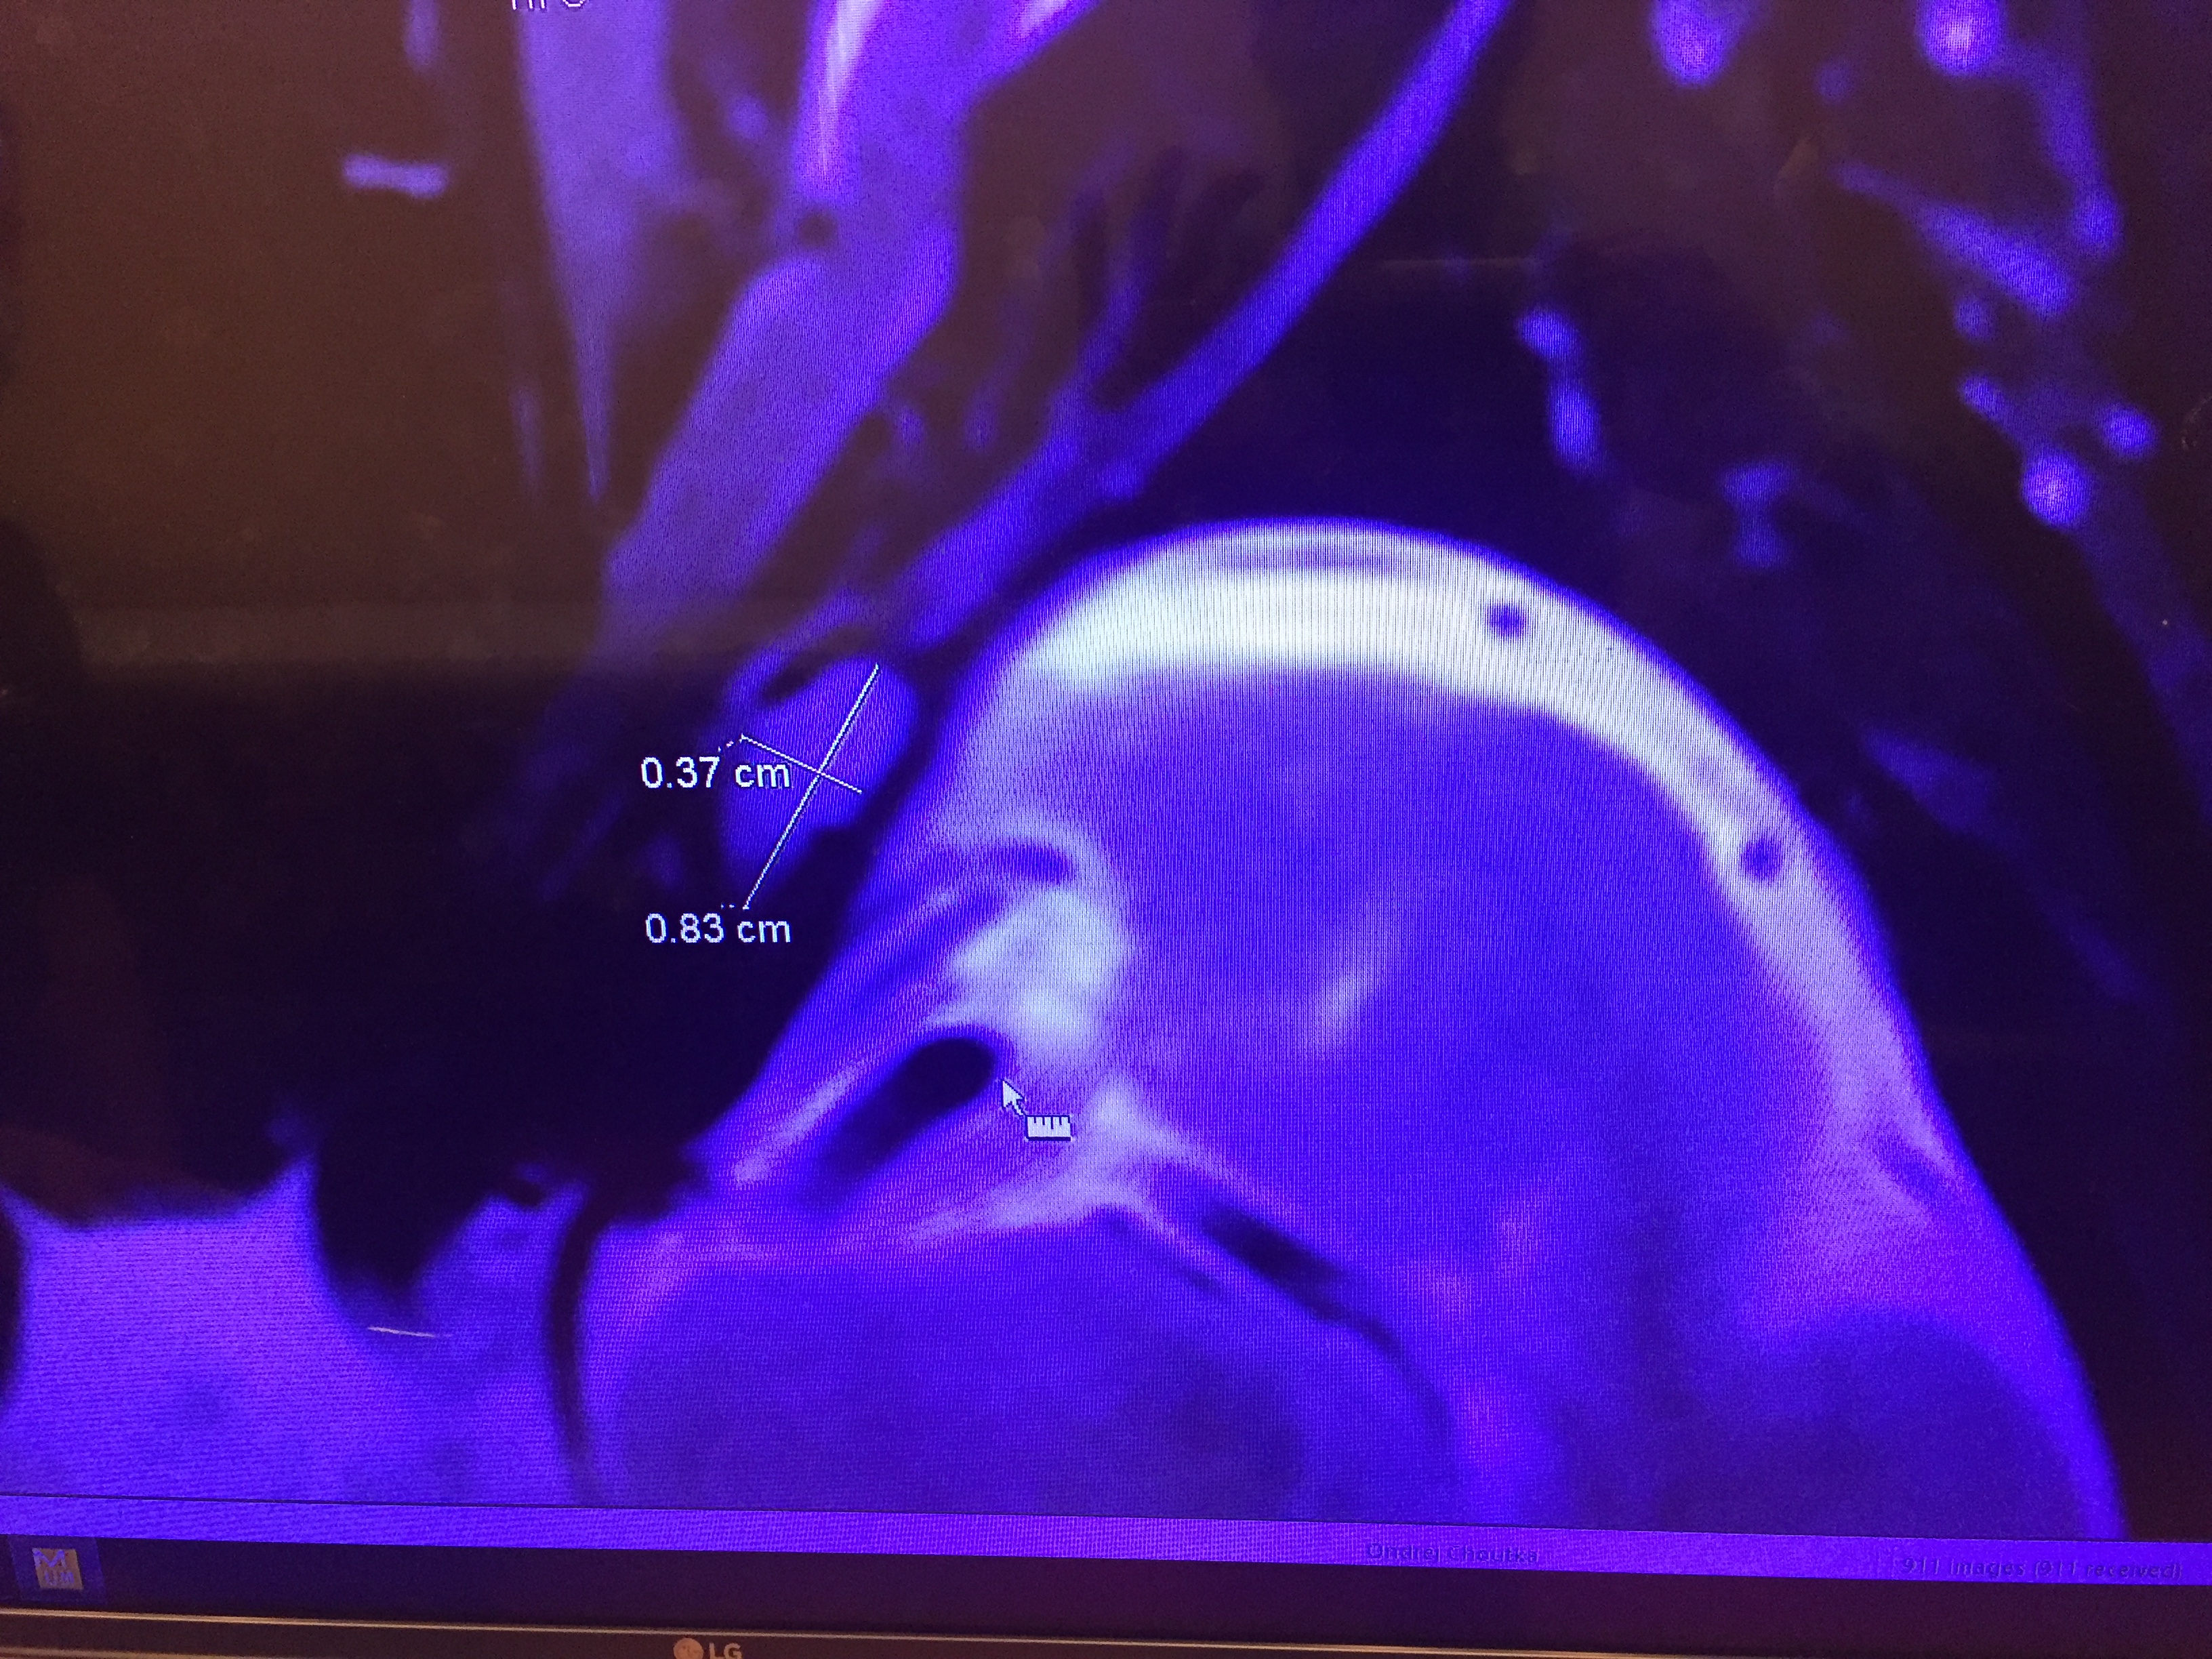

What causes the nerve to stop working? According to my dad's neurologist, a few things: Something that is a nuisance but will go away (like a viral infection), something benign (like a cyst), or something terrifying (like cancer). Because his condition continued to deteriorate, a viral cause was unlikely. To help aid the diagnosis, my dad got an MRI, depicted below:

As shown, the doctor observed an unusual growth that was 0.37 cm by 0.83 cm located near the left sixth cranial nerve. Because the growth didn't get any bigger over time, it is (thankfully) unlikely to be cancer. That leaves the last option: Something benign is pushing against the nerve. The doctor thinks it's a non-malignant tumor.